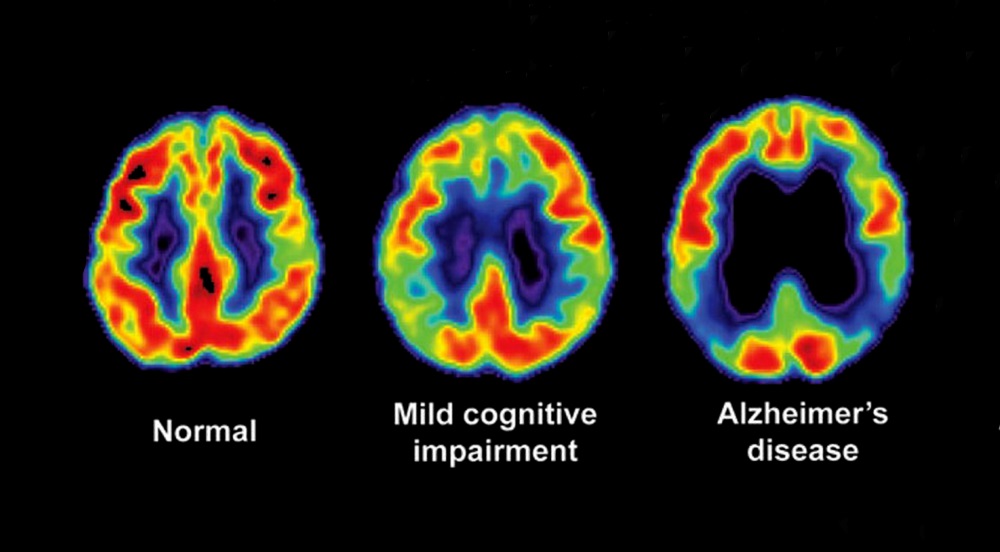

stages alzheimer brain mri disease alzheimers

disease alzheimer alzheimers dementia